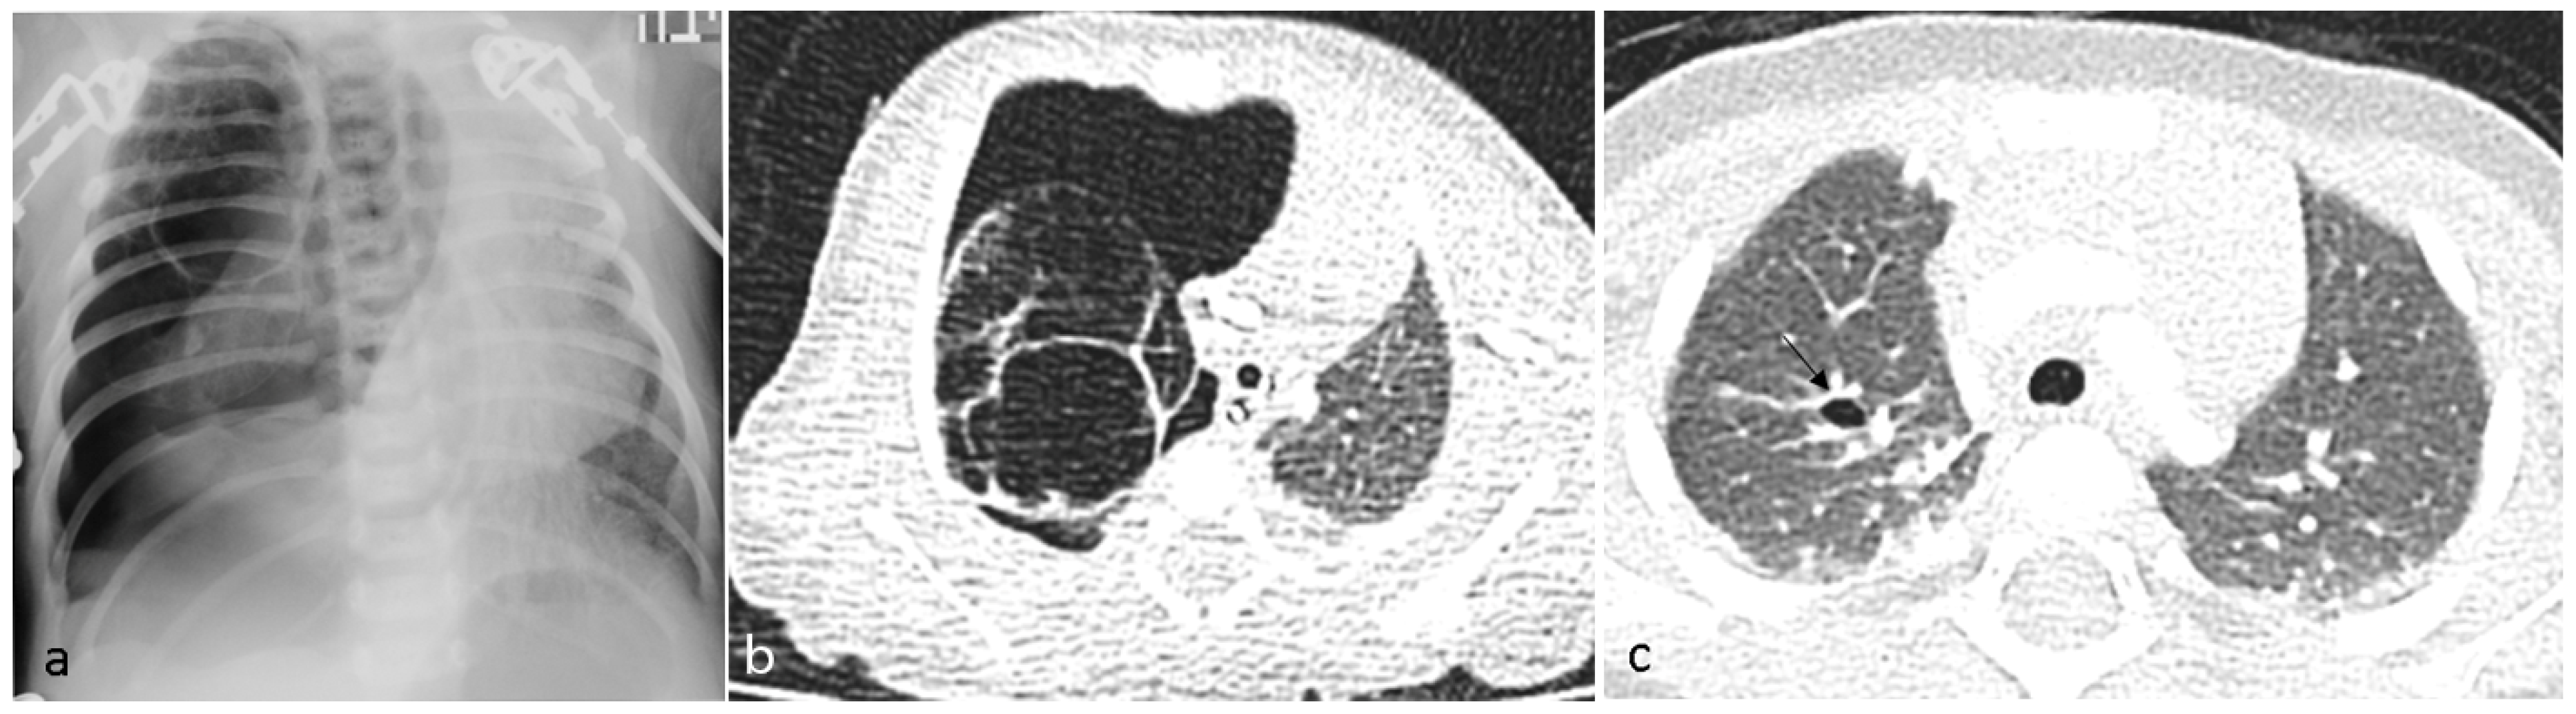

Subcutaneous Emphysema in COVID19 Managed with Surgical Tracheostomy A Case Series

Cureus ClopidogrelAssociated Interstitial Lung Disease A Case Report and Literature Review Does Fiberglass Dissolve In Lungs   fiberglass inhalation seems to produce a minimal tissue response in the lungs, and the reaction is one of macrophagic.   in this blog post, we will dive deep into the question, “does fiberglass stay in your lungs forever?” we will explore the.  the mediastinal lymphadenopathy and the pulmonary infiltrates resolved after cessation of fiberglass exposure. Ingested fiberglass is. Does Fiberglass Dissolve In Lungs.